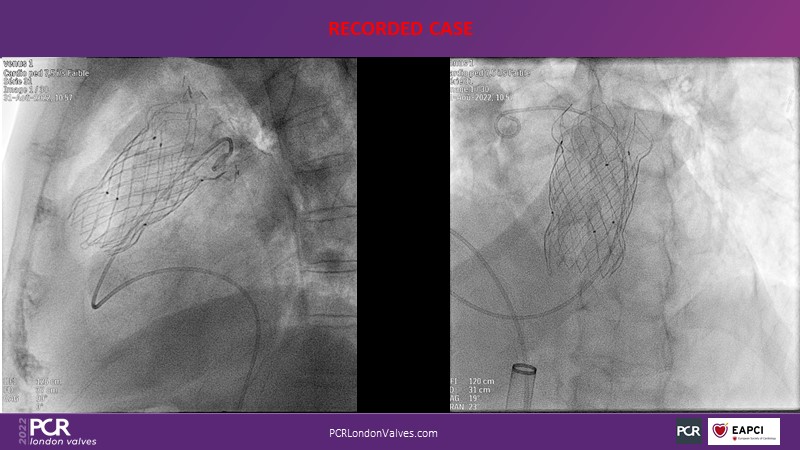

The right valves for the right ventricle: Venus MedTech tricuspid and pulmonary replacement systems

In this session from PCR London Valves 2022, discover the new Venus MedTech technology for tricuspid and pulmonary valve replacement, and a review of the clinical indications, selection criteria and procedural details.